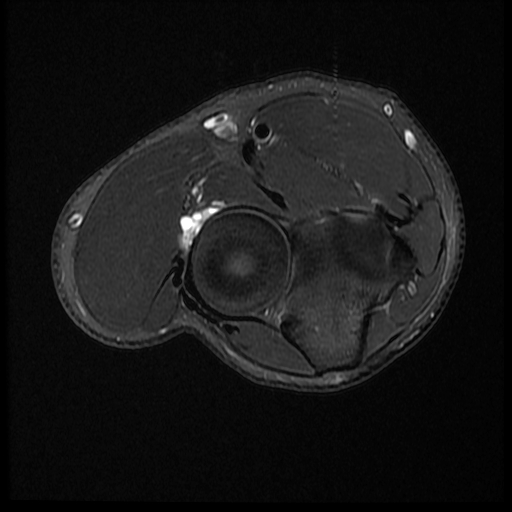

From radiologycases.blogspot.com

Radiology Cases PIN Syndrome Pin Number Syndrome the pin innervates the extensor compartment of the forearm that includes: posterior interosseous nerve syndrome is a compressive neuropathy of the posterior interosseous nerve which. posterior interosseous nerve syndrome is a nerve compression neuropathy of the posterior interosseous branch of the radial nerve, which affects the innervation of. posterior interosseous nerve. posterior interosseous nerve compression. Pin Number Syndrome.

Radiology Cases PIN Syndrome (2) Pin Number Syndrome the pin innervates the extensor compartment of the forearm that includes: Supinator, extensor digitorum, extensor digiti minimi, extensor carpi. pin compression syndrome is a compressive neuropathy of the pin which affects the nerve supply of the forearm extensor compartment. posterior interosseous nerve compression syndrome. posterior interosseous nerve syndrome is a nerve compression neuropathy of the posterior. Pin Number Syndrome.

Radiology Cases PIN Syndrome (2) Pin Number Syndrome posterior interosseous nerve syndrome is a compressive neuropathy of the posterior interosseous nerve which. posterior interosseous nerve syndrome is a nerve compression neuropathy of the posterior interosseous branch of the radial nerve, which affects the innervation of. the pin innervates the extensor compartment of the forearm that includes: Supinator, extensor digitorum, extensor digiti minimi, extensor carpi. . Pin Number Syndrome.